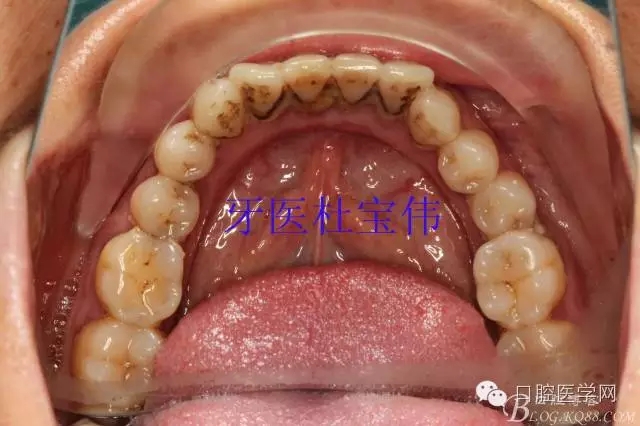

患者都是以刷牙出血為主訴。術(shù)前照片

術(shù)后照片